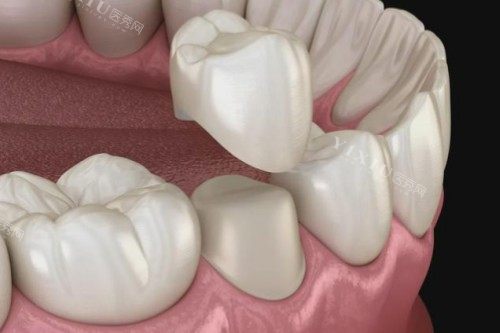

八、牙冠修复项目

• 金属烤瓷冠:1500元/颗(钴铬合金内冠)

• 全瓷冠(爱尔创):2400元/颗(透光度达40%)

• 威兰德玻璃陶瓷:3200元/颗(前牙美学修复)

• LAVA二氧化锆:4500元/颗(抗压强度超1200MPa)

• 氧化铝全瓷冠:3800元/颗(兼顾强度与美观)

技术亮点:智能化比色系统,色差控制在ΔE<1.5,避免“假牙感”。